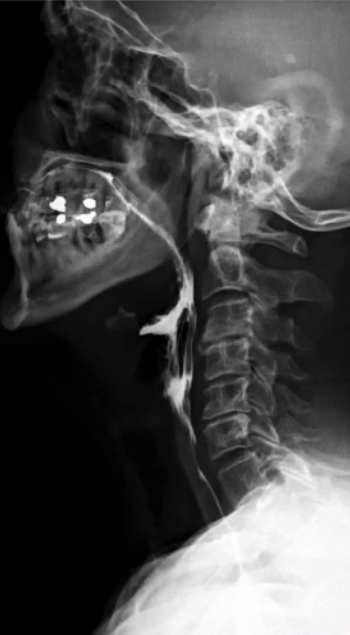

Transit oesophagien et gestro-duodénal (TOGD)

Cet examen permet de visualiser la progression d’un produit opaque au niveau de l’œsophage, de l’estomac et du duodénum et d’étudier les parois digestives.